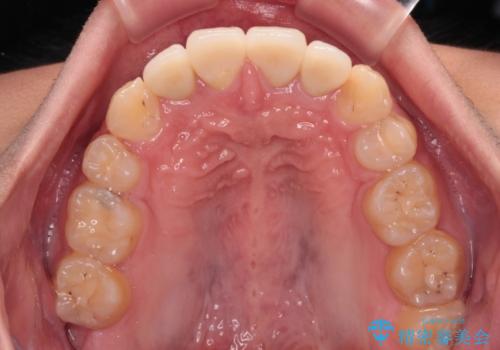

矯正治療後は上顎前歯4本をオールセラミッククラウンにて補綴治療を行うこととしました。

むし歯が多かったため、ワイヤー矯正中に処置したむし歯が悪化することが懸念されましたが、歯磨きをしっかりと行ってくれたため、とても良好な状態を維持することができました。